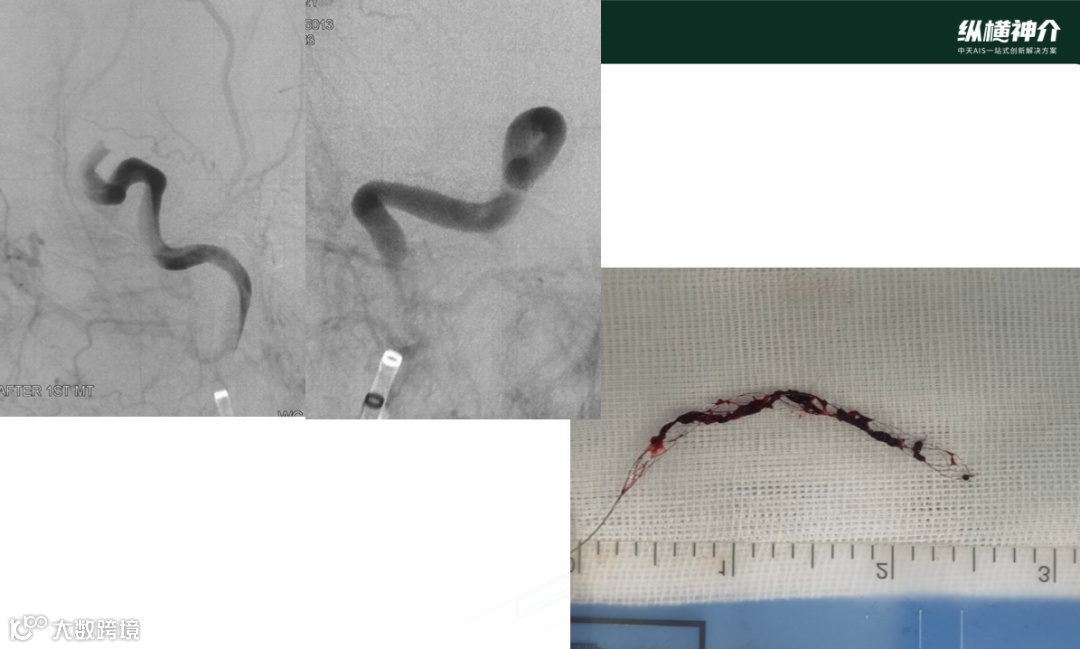

病例二

• 天弋®取栓支架 6*40mm 4*30mm

• 微导管在到达远端后,造影发现M2处也有血栓存在

• 天弋® 6*40mm取栓支架到位释放打开,显影性非常好,相比其他尺寸,对大负荷量血栓具有优势

• 天弋®取栓支架从近端到远端是缠绕血栓,而没有被近端血栓刮除掉

• 二次取栓操作,大脑中和颈内动脉血栓进一步减容

• 第三次取栓

• 天弋®取栓支架 4*30mm

• 抓捕的血栓效果来看,血栓是一个旋转的形态,用手去取下支架上的血栓比较难以取下,需要把血栓碾碎后取下。支架与血栓粘结非常紧密,临床表现优异